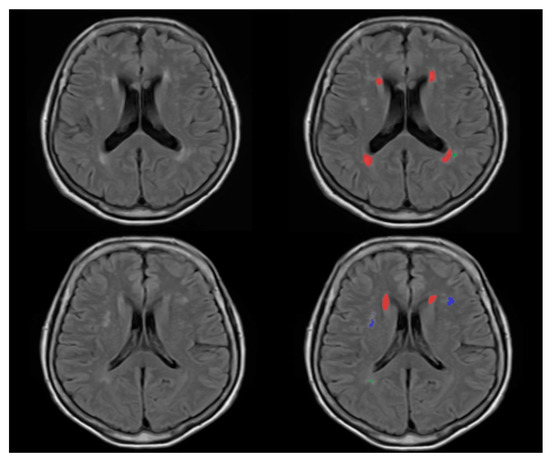

2.4. WMH Segmentation